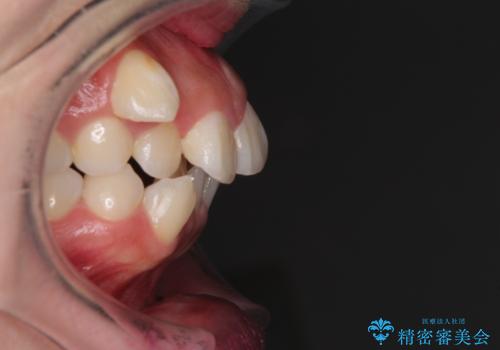

著しい叢生と顎骨のズレ ワイヤー装置による抜歯矯正

- 前歯の著しい叢生や八重歯を気にして来院された患者様です。

上下の顎がずれており、上下の正中は歯1本分の差がありました。

上下左右の小臼歯4本を抜歯し、極力正中を合わせるように矯正治療を始めていくこととしました。

咬み合わせの乱れが著しく、治療途中で一部反対咬合となってしまいました。

アンカーなどをうまく使用して、3年の期間を要してきれいに仕上げることができました。